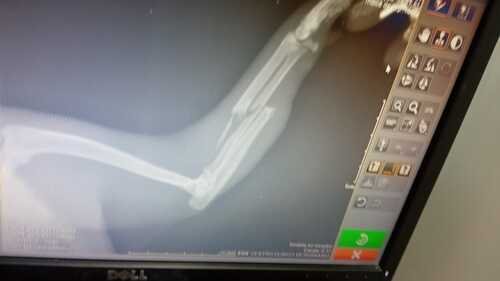

O Sheldon, gatinho da minha mãe quebrou a patinha e foi levado para o veterinário com urgência. O valor total dos exames, Raio X, sedação, procedimento de colocar a tala e medicação para recuperação ficou R$900,00. Sua ajuda com qualquer quantia em dinheiro fará toda a diferença. Desde já agradeço a todos que ajudarem.